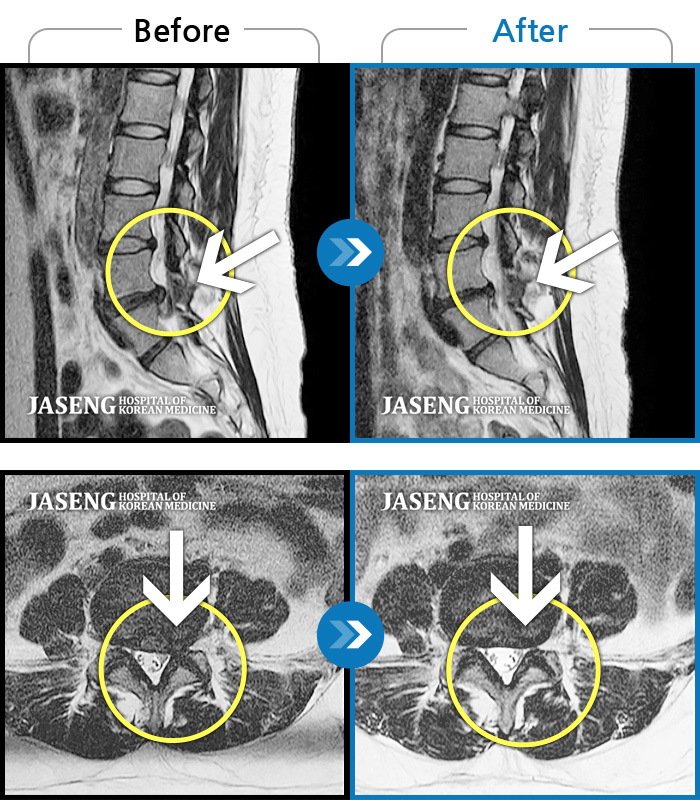

MRI 치료사례

급성허리통증으로 내원